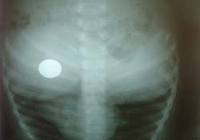

Eğer Çocuğunuz Bozuk Para Yutarsa Ne Yapacaksınız ?

Sevgili melekler, çocuklar ömür törpüsüdür derler ya büyükler, ne kadar da haklılar. Öyle zaman geliyor ki ömrümüzden yılları alıp götürüyorlar bize yaşattıkları korkularla.:hıms: En çok korkulan ve ne yazık ki her zaman hepimizin başına gelebilecek tehlikelerden biri de ev kazaları. Özellikle küçük çocuğunuz varsa bu kazalar kaçınılmaz olabiliyor. Elbette ki gerekli önlemleri almak çok önemli ama çocuk işte, kaşla göz arası yapacağını yapıyor. 🙂 Bu sayfamızda önemli bir konu Çocuğun Bozuk Para Yutması durumunda neler yapılabileceğini anlatmak istiyoruz sizlere...